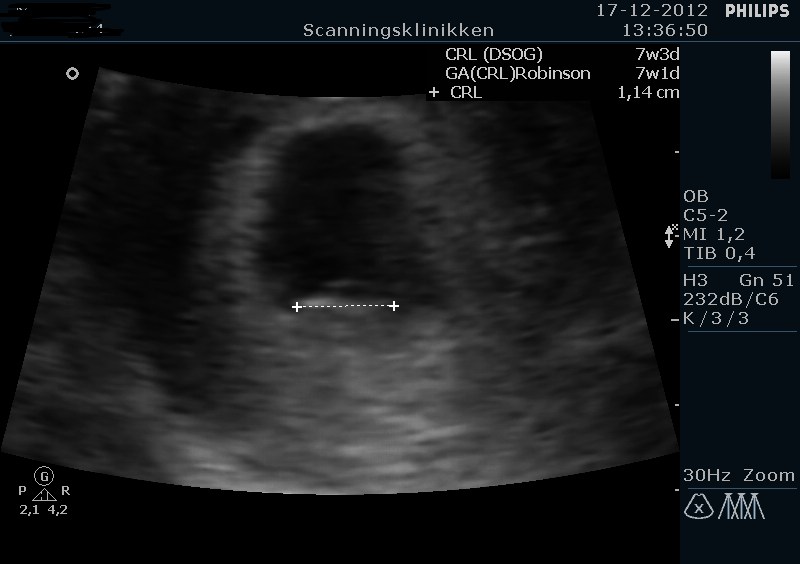

Så har jeg været til tidlig tryghedsscanning i dag - selv betalt selvfølgelig

Jeg blev sat én dag frem så den hedder 7+3 i stedet for 7+2 lige pt. Det kan jo sagtens nå at ændre sig

Jeg gik selvfølgelig lidt i panik i morges da der var en meget lille smule blod på papiret, så man kan vel sige held i uheld at vi skulle ind i dag. Heldigvis lå der en fin lille peanut derinde med flot hjerteblink, så det var super dejligt

Vedhæfter lige billeder